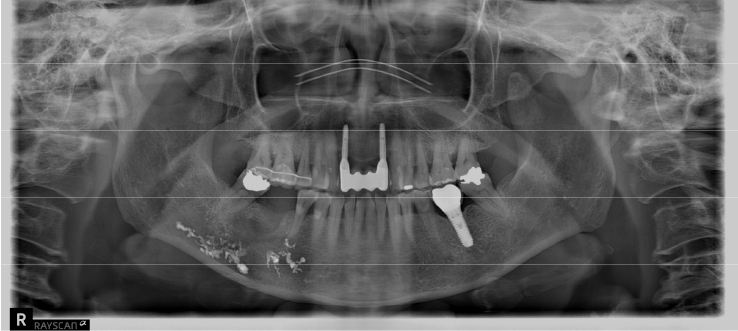

An 18-year-old male developed numbness in the right lower lip, gingiva, and chin following endodontic treatment of the mandibular right first molar (#46) at a military hospital 2 weeks ago. A panoramic radiograph and multi-detector computed tomography (MDCT) revealed extruded Calcipex II in proximity to the IAN (Fig. 6). Neurologic testing confirmed severe hypoesthesia in the right mentum region. Thermal discrimination was absent across a broad area of the right lower lip and chin. The patient’s subjective discomfort was rated as VAS 2. The patient underwent foreign body removal, nerve transposition, and bone grafting under general anesthesia (Fig. 7). At one-week postoperative follow-up, neurosensory testing showed little to no improvement. At the five-month follow-up, repeated neurosensory testing demonstrated meaningful improvement in directional discrimination and pin-pressure nociceptive discrimination, despite the continued presence of hypoesthesia. At the 17-month follow-up, testing revealed further improvement, including recovery of static light touch sensation, with overall symptoms classified as mild hypoesthesia. However, the patient reported worsening subjective discomfort, with a VAS 5, reflecting a discordance between objective sensory recovery and subjective symptom persistence.